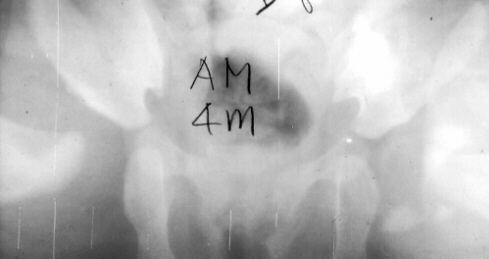

A two month old child had been treated with a Pavlik Harness for a dislocated hip since age of 10 days. After 2 months, the left hip remained dislocated. Home traction was started. An arthrogram, adductor tenotomy and closed reduction was done at 4 months of age. Single hip spica was applied with the hip in 40 degrees of abduction and 100 degrees of flexion. Four months later, the spica cast was removed and an Atlanta brace was applied. X-rays showed avascular necrosis (AVN) at ten months of age.

The AVN was most likely caused by the early use of the Pavlik harness.